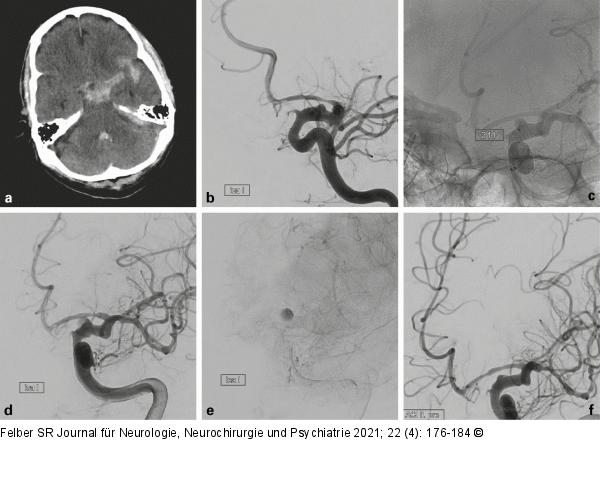

Abbildung 7a-f: Blister-Aneurysma Der 72-jährige Patient wurde nach einem Sturz mit nachfolgender Vigilanzminderung auswärts intubiert. Die CT bei Aufnahme (a) zeigte eine Subarachnoidalblutung links bis in die insuläre Zisterne reichend. Die Angiographie ergab ein 3 mm großes Blister-Aneurysma der intraduralen A. carotis interna links (b). Das Blister-Aneurysma wurde mit zwei Flow Divertern überdeckt (p64 4,5 × 24 mm und 4,5 × 21 mm, Phenox, Bochum, Deutschland) (c), danach zeigte sich Kontrastmittelstase im Aneurysma (d, e). Aufgrund zunehmender Vasospasmen wurde nach 3 Tagen eine intraarterielle Spasmolyse (Nimotop S, Bayer Vital, Leverkusen, Deutschland) durchgeführt. Dabei zeigte sich das Aneurysma bereits fast vollständig rückgebildet (f). |

Abbildung 7a-f: Blister-Aneurysma